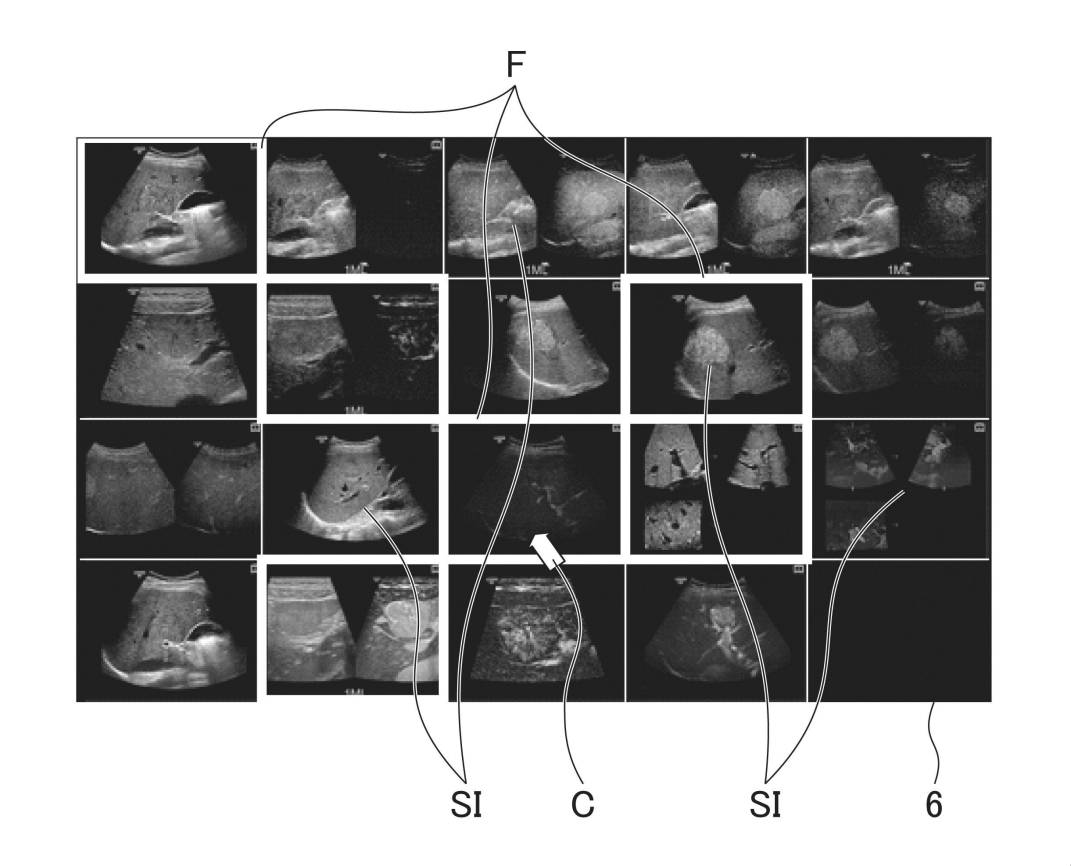

超音波診断装置及びその制御プログラム